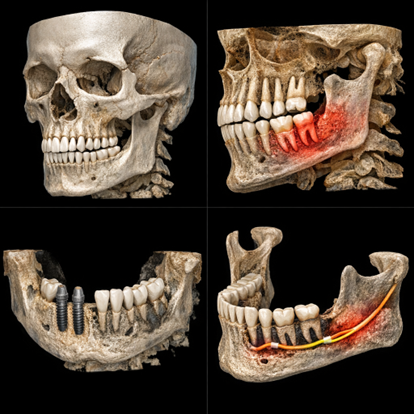

3D CBCT scans

Clinical evaluation

This detailed approach ensures accurate planning, safer procedures, and predictable outcomes.

1. Consultation & Scan – Your dentist evaluates your jawbone using X-rays or 3D scans to determine the need for grafting and plan the procedure.